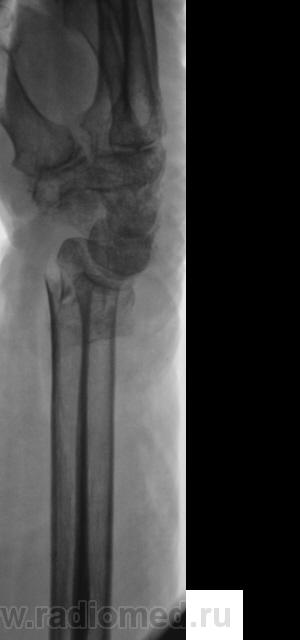

Травма. Пациентка направлена врачом хирургом на рентгенографию лучезапястного сустава.

На фоне умеренных артрозных изменений в л/з и мелких суставах кисти оскольчатый в/суставной разгибательнуй перелом лучевой кости в т.м. с резко выраженным смещением под углом (около 120 гр), открытым дорзально. Перелом шиловидного отростка локтевой кости. Плохо вижу контур крючковатой кости по ульнарной поверхности.

Пациент направлен на рентгенографию лучезапястного сустава.

Вколоченный (или сколоченный) перелом лучевой кости с удовл. стоянием к/фрагментов неясной давности. в дист. отделах костей предплечья и, по-моему, костях запястья умеренный остеопороз. Очаг дестукции в головке 5-й пястной ? (вижу нечетко, погрешность передачи изображения?)

Заслуживают также внимание 4 и 5 пястные кости, особенно 4 пястная кость.

4 пястная грацильна, но структуру ее , к сожалению, рассмотреть не удается.Кроме остеопороза в ее проксим. конце и истончения кортикального слоя ничего не вижу.